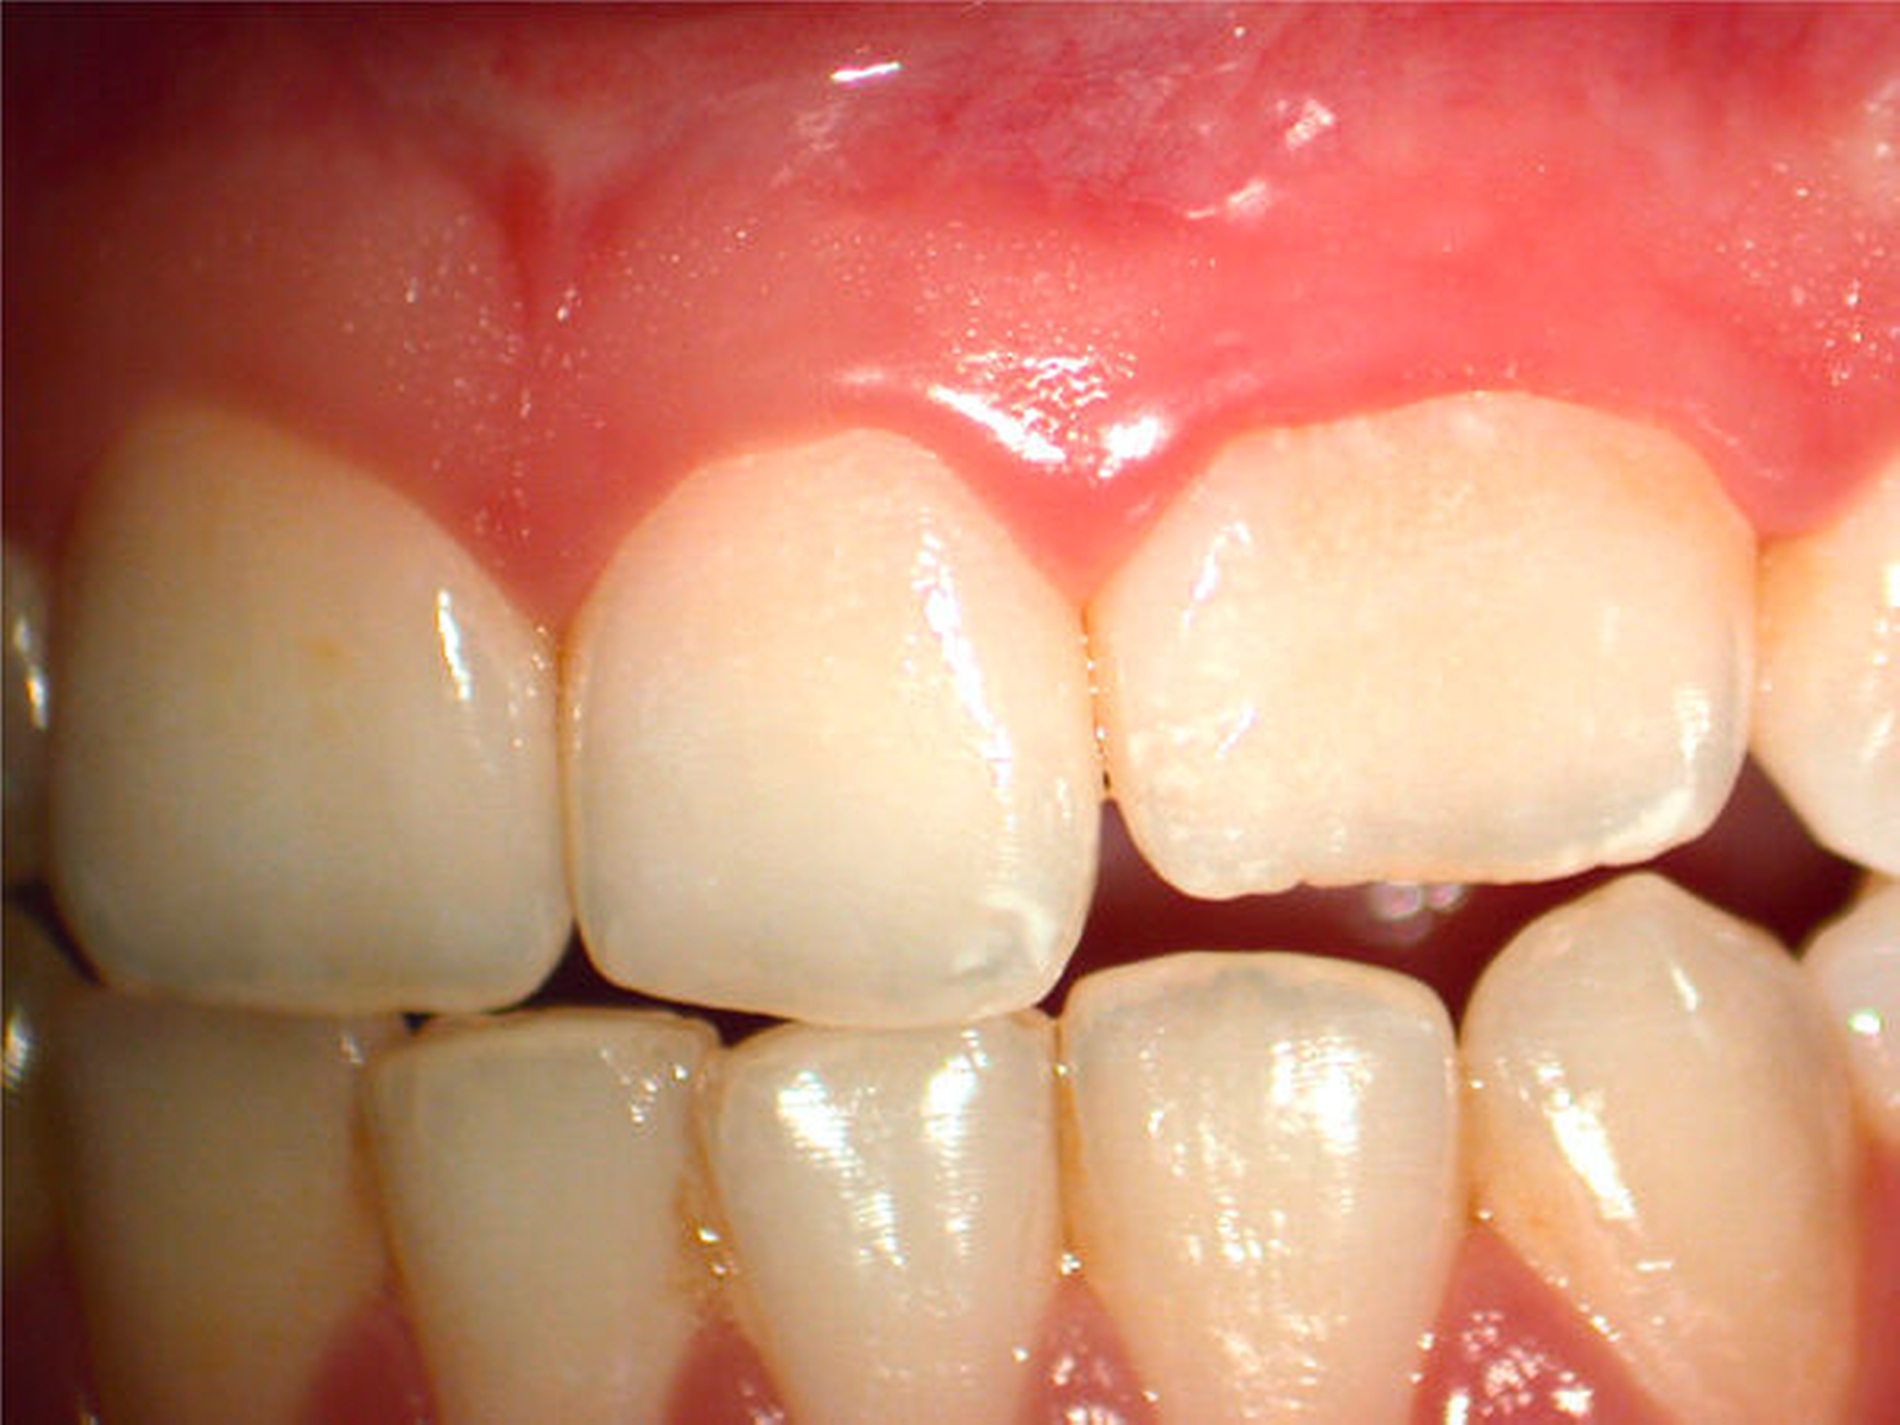

Erste Hinweise auf mögliche Formabweichungen oder Anomalien der Wurzel sind häufig an der äußeren Form der klinischen Zahnkrone zu erkennen [Mueller, 1933; Schulze, 1987]. Insbesondere auf der palatinalen Fläche sind bei einem ausgeprägten Tuberculum dentis oder einem Foramen caecum weitergehende diagnostische Untersuchungen nötig, um rechtzeitig Form- und Strukturveränderungen der Zähne erkennen zu können (Abbildungen 6 bis 8).

Zapfenförmige seitliche Schneidezähne können ein Hinweis auf eine abweichende Form des Wurzelkanalsystems sein. So können mehrfach gekrümmte Wurzelkanäle beobachtet werden. Darüber hinaus können auch Fehlentwicklungen des äußeren Schmelzepithels auftreten und als Ursache für scheinbar untypische pulpitische Beschwerden bei fehlender Karies verantwortlich sein (Abbildung 13). Invaginationen des äußeren Schmelzepithels können in unterschiedlich tiefer Ausprägung auftreten [Tomas, 1974]. Die Prävalenz dentaler Invaginationen liegt zwischen 3 und 10 Prozent, wobei sie in bis zu 70 Prozent der Fälle bilateral auftreten [Thomas, 1974; Gotoh, 1979; Hülsmann, 1995]. Nach Oehlers werden drei Grade unterschieden [Oehlers, 1957]. Insbesondere Typ-II-Invaginationen mit einer Einstülpung bis unterhalb der Schmelz-Zement-Grenze können bei mikrobieller Infektion aufgrund der Nähe zur Pulpakammer eine irreversible Pulpitis und eine nachfolgende Pulpanekrose auslösen. Im Fall eines Dens invaginatus vom Typ III besteht zwischen der Eintrittspforte an der klinischen Zahnkrone und dem apikalen Endpunkt ein vom Wurzelkanal unabhängiger Verlauf [Hülsmann, 1995]. Die Infektion eines Dens invaginatus kann deshalb röntgenologisch zu einer periapikalen Aufhellung bei fortbestehender Sensibilität des Zahnes führen (Abbildung 14). Eine minimalinvasive Invaginationstherapie kann den Erhalt der Pulpa ermöglichen (Abbildung15).

Bei einem ausgeprägten Foramen caecum sollte eine weitere anatomisch-morphologische Variation in die Differenzialdiagnostik – zur Abklärung eventueller anatomischer Besonderheiten – einbezogen werden: In Verlängerung des Tuberculum dentis kann sich eine Fissur über die Schmelz-Zement-Grenze hinaus auf der Wurzeloberfläche fortsetzen. Je nach Ausprägung können diese Wurzelfurchen auch den Beginn von Wurzelseparationen darstellen. Im Ergebnis der Einfaltung des Schmelzepithels und der Einschnürung im Bereich der Hertwigschen Wurzelscheide enwickelt sich in seltenen Fällen eine rudimentäre oder vollständig ausgebildete Wurzel [Black, 1908; Arnold, 2007; Gandhi et al., 2011]. In seltenen Fällen können einwurzelige Zähne mit zwei oder mehr Wurzelkanälen [Kottoor et al., 2012] oder zweiwurzelige Zähne mit zwei Wurzelkanälen auftreten [Fabra-Campos, 1990] (Abbildung 17).